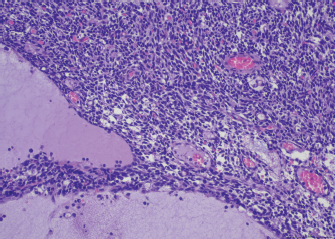

A 4-year-old spayed female mixed-breed dog was referred with a 1-month history of regurgitation and progressive generalized weakness. At the time of presentation, the general physical examination was unremarkable. The neurologic examination revealed exercise intolerance, with the development of weakness beginning in the hindlimbs and progressing into a non-ambulatory flaccid tetraparesis with neck ventroflection, which was alleviated by rest and bilateral symmetrical reduction of patellar, tibialis cranialis, and withdrawal of reflexes. The dog showed mild dysphagia characterized by reduced and difficult swallowing and hypersalivation. The neurologic exam was indicative of a generalized lesion of the low motor neuron system. The neurologic examination was followed by an extended laboratory analysis, including blood counts, serum biochemical profile, coagulation and urinary analysis, and chest radiographs. The haematological abnormalities were a mild increase of WBC (13.1; reference ranges (RR): 5.37–12.39 × 103/mcl) characterized by neutrophilia (11,135; RR: 2,778–8,220 × 103/mcl), lymphocytosis (1,179; 1,009–3,471 × 103/mcl), and monocytosis (655; RR: 155–537 × 103/mcl). Biochemistry revealed significant increase in creatine kinase (CK) (7,934; 39–168 U/l) with a less severe increase of aspartate aminotransferase (AST) (389; 16–39 U/l) and alanine aminotransferase (ALT) (302; 15–79 U/l), moderately elevated C reactive protein (4.54; RR: 0.01–0.41 mg/dl), and hyperferritinemia (776; RR: 38–272 ng/ml). Urinalysis was within normal limits. The thoracic radiographs showed a diffusely dilated esophagus and soft tissue opacity in the cranial mediastinum. The diagnostic suspicion was a form of acquired MG associated with a cranial mediastinal mass although clinically polymyositis could not be completely excluded. A 0.05 mg/kg (0.02 mg/lb) of neostigmine (Prostigmina®) was administered intramuscularly to support our first suspicion. After few minutes, the dog showed a positive result, with increased muscular strength. A computed tomographic (CT) scan examination showed a rounded cranial mediastinal neoformation, characterized by heterogeneous appearance due to the presence of cystic intraparenchymal areas and associated with normal cranial sternal and mediastinal lymph nodes. The CT scan also showed an expansion of the entire esophagus and stomach, mainly due to gas. These findings confirmed a moderate megaesophagus and the presence of a cranial mediastinal mass. A cytological examination and, subsequently, a tru-cut biopsy of the mediastinal mass was performed both with non-diagnostic results. Serum antibodies against ACHRs were highly supportive of MG (5.23 nmol/l; normal in dogs < 0.6 nmol/l). The dog was treated with neostigmine therapy (Prostigmina®) at 0.01 mg/kg (0.004 mg/lb) IM q8h, showing mild improvement of muscular weakness. The cranial mediastinal mass was surgically excised by a median sternotomy. Histology of the formalin-fixed specimen revealed a capsulated, well demarcated, not infiltrative neoplasm, composed of sheets and cords of mildly pleomorphic, spindle to oval cells, multifocally lining variably sized cystic spaces, often filled with eosinophilic secretory material. Neoplastic cells were associated with a moderate number of lymphocytes, forming small multifocal aggregates (Fig. 1). To further characterize the neoplasm, immunohistochemistry was performed using the automated immunostainer Bond RX (Leica Biosystem, Nussloch GmbH; Nusloch, Germany). Antibodies manufacturer, source, clone and dilution are listed in Table 1. The antigen unmasking technique was performed as indicated by the manufacturer. Neoplastic cells were found to express cytokeratin, which exhibited strong cytoplasmatic staining within neoplastic cells lining the cysts, while having a weak to moderate intensity in solid areas. Rare aggregates of desmin and muscle actin expressing cells, interpreted as myoid cells, were also detected.

Fig. 1. Thymoma, dog. Sheets of neoplastic spindle cells are lining multifocal cystic lacunae. Hematoxylin and eosin.